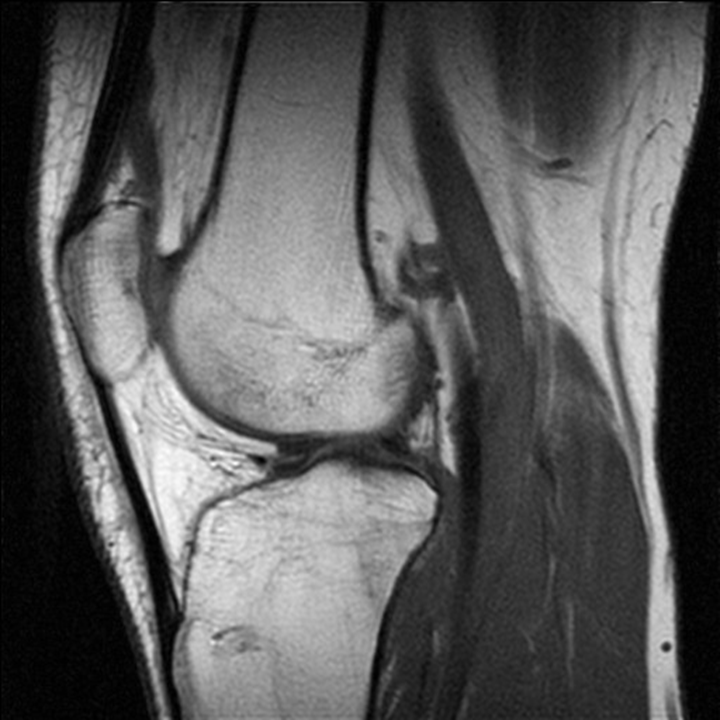

СУГЛОБ СКЛАДНИЙ. СУГЛОБОВА КАПСУЛА ТОНКА, УТВОРЮЄ БАГАТО СУМОК, ЯКІ СПОЛУЧАЮТЬСЯ ІЗ СУГЛОБОВОЮ ПОРОЖНИНОЮ. ЦЕ СПРИЯЄ ПЕРЕХОДУ ЗАПАЛЬНИХ ПРОЦЕСІВ (Є ДІАГНОЗ: БУРСИТ). ДЕ ВИ БАЧИТЕ ЦЕЙ СУГЛОБ.

варіанти відповідей